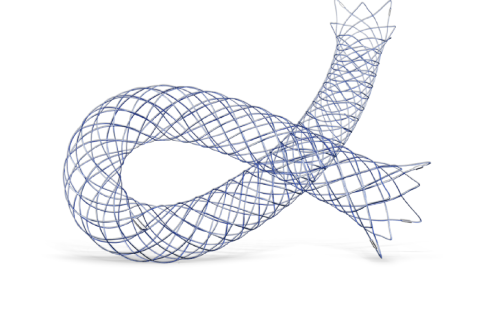

Em Cirurgia Vascular, Endovascular e Radiologia Intervencionista oferecemos uma ampla gama de soluções, incluindo enxertos endovasculares, cateteres de trombectomia e dispositivos de embolização. Esses produtos são vitais para o tratamento de doenças vasculares complexas, como aneurismas e tromboses, proporcionando aos profissionais de saúde as ferramentas necessárias para intervenções precisas e eficazes.

Nossa atuação em Neurorradiologia Intervencionista inclui a oferta de microcateteres e stents especializados para o tratamento de aneurismas cerebrais e outras condições neurológicas críticas. Esses dispositivos são desenvolvidos com tecnologia de ponta para garantir a máxima segurança e eficácia durante os procedimentos, ajudando a preservar a integridade cerebral dos pacientes.